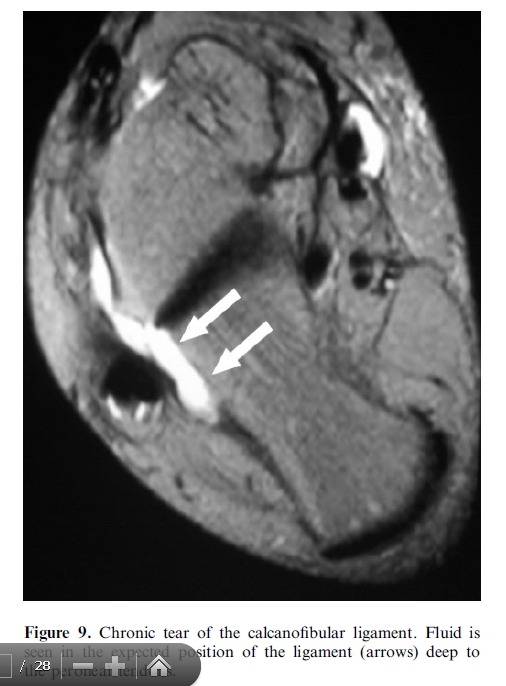

Imaging plays a major role in the management of ankle and foot problems. Most conditions are assessed by plain

films alone. MRI is an excellent technique for those cases where the diagnosis is uncertain as it can exclude most

clinically relevant pathologies. Ultrasound is an excellent tool for imaging focal soft tissue abnormalities. CT is

occasionally useful when bony detail is required. Bone scintigraphy has a limited role and has been largely replaced by MRI in many centres. The main reasons for referral are swelling and pain. Many conditions of the ankle and foot are related acute or repetitive trauma.

# MRI is the most suitable technique for global assessment of bone and soft tissues for persistent pain following injury.